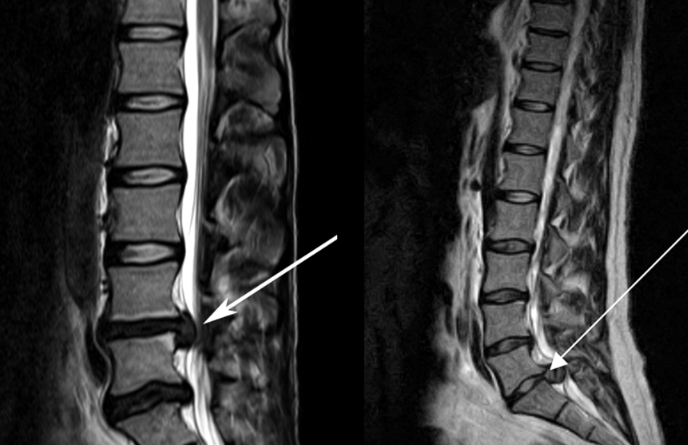

關(guān)于腰椎間盤突出  腰椎間盤突出癥是纖維環(huán)破裂后髓核突出壓迫神經(jīng)根造成以腰腿痛為主要表現(xiàn)的疾病。腰椎間盤退行性改變或外傷所致纖維環(huán)破裂,髓核從破裂處脫出,壓迫腰椎神經(jīng),從而出現(xiàn)腰腿放射性疼痛。  病因: 一、退行性變: 目前認(rèn)為,其基本病因是腰椎間盤的退行性變。退行性變是一切生物生、長、衰、亡的客觀規(guī)律,由于腰椎所承擔(dān)的特殊的生理功能,腰椎間盤的退行性變比 其他組織器官要早,而且進(jìn)展相對要快。這個過程是一個長期,復(fù)雜的過程。所謂腰椎間盤退行性改變:即由于椎間盤受體重的壓迫,加上腰部又經(jīng)常進(jìn)行彎曲、后伸等活動,易造成椎間盤的擠壓和磨損,尤其是下腰部的椎間盤,從而產(chǎn)生退行性改變。腰椎間盤退行性改變是本病發(fā)生的基礎(chǔ)。 二、其他因素: 1、外力作用:在日常生活和工作中,部分人往往存在長期腰部用力不當(dāng)、過度用力姿勢或體位的不正確等情況。例如長期從事彎腰工作的煤礦工人和建筑工人需經(jīng)常彎腰提舉重物。這些長期反復(fù)的外力造成的損傷日積月累地作用于椎間盤,加重了退變的程度。 2、椎間盤自身解剖因素的弱點: (1) 椎間盤在成人之后逐漸缺乏血液循環(huán),修復(fù)能力也較差,特別是在退變產(chǎn)生后,修復(fù)能力更加微弱。 (2) 椎間盤后外側(cè)的纖維環(huán)較為薄弱,而后縱韌帶在腰5、骶1平面時寬度顯著減少,對纖維環(huán)的加強(qiáng)作用明顯減弱。 (3) 腰骶段先天異常:腰骶段畸形可使發(fā)病率增高,這些異常造成椎間隙寬度不等,并常造成關(guān)節(jié)突出,關(guān)節(jié)受到更多的旋轉(zhuǎn)勞損,使纖維環(huán)受到的壓力不一,加速退變。 3、種族、遺傳因素:有色人種發(fā)病率較低,例如印第安人和非洲黑人等發(fā)病率較其他民族明顯要低。  2 病理 腰椎間盤突出癥的病理變化過程大致可分為三個階段: 1、突出前期:髓核因退變和損傷可變成碎塊狀物,或呈瘢痕樣結(jié)締組織,變性的纖維環(huán)可因反復(fù)損傷而變薄變軟或產(chǎn)生裂隙。此期病人可有腰部不適或疼痛,但無放射性下肢痛。也有的人原無病變,可因一次大的暴力引起髓核突出。 2、突出期:外傷或正常的活動使椎間盤壓力增加時,髓核從纖維環(huán)薄弱處或破裂處突出。突出物刺激或壓迫神經(jīng)根即發(fā)生放射性下肢痛,或壓迫馬尾神經(jīng)發(fā)生大小便功能障礙。在老 年患者,可因椎間盤退變,整個纖維環(huán)變得軟弱松弛,椎間盤可呈彌漫性向周圍膨出。 3、突出晚期:腰椎間盤突出后,病程較長者,椎間盤本身和其他鄰近結(jié)構(gòu)均可發(fā)生各種繼發(fā)性病理改變。 3 誘發(fā)因素 腰椎間盤突出癥的基本因素是椎間盤退變,但某些誘發(fā)因素可致使椎間隙壓力增高,引起髓核突出。此種誘發(fā)因素常與以下因素有關(guān): 1. 年齡因素:腰椎間盤突出癥的好發(fā)年齡在30-50歲,平均手術(shù)年齡在40歲,因此退變可能是其重要因素。 2. 身高與性別:有人認(rèn)為身材過高也會易發(fā)腰突癥,而男性發(fā)病率是女性的5倍。 3. 增加腹壓:臨床上有約1/3的病人在發(fā)病前有明確的增加腹壓的因素,如劇烈的咳嗽、噴嚏、屏氣、用力排便等。使腹壓增高,破壞了椎節(jié)與椎管之間的平衡狀態(tài)。 4. 不良體位:人在完成各種工作時,需要不斷更換各種體位以緩解腰部壓力,如長期處于某一體位不變,即可導(dǎo)致局部的累積性損傷。特別是長期處于不良姿勢更容易誘發(fā)本病。 5. 職業(yè)因素:重體力勞動者發(fā)病率最高,白領(lǐng)勞動者最低。汽車駕駛員由于長期處于顛簸和振動狀態(tài),椎間盤承受的壓力大且反復(fù)變化,也易誘發(fā)椎間盤突出。 6. 受寒受濕:寒冷或潮濕可引起小血管收縮、肌肉痙攣,使椎間盤的壓力增加,可能造成退變的椎間盤破裂。     癥狀: 腰椎間盤突出癥患者最多見的癥狀為疼痛,可表現(xiàn)為腰背痛、坐骨神經(jīng)痛,典型的坐骨神經(jīng)痛表現(xiàn)為由臀部、大腿后側(cè)、小腿外側(cè)至跟部或足背的放射痛。據(jù)臨床統(tǒng)計,約95%的腰突癥患者有不同程度的腰痛,80%的患者有下肢痛。特別是腰痛,不僅是腰椎間盤突出最常見的癥狀,也是最早出現(xiàn)的癥狀之一。    檢查: 1、X線:腰椎間盤所包括的髓核、纖維環(huán)和軟骨板密度均較低,在X線下并不顯影,因此臨床上腰突癥患者的腰椎X線平片可僅有一些非特異性的變化,甚至無異常變化。因此單純腰椎平片并不能作為有無腰椎間盤突出癥的直接依據(jù),但X線能發(fā)現(xiàn)腰椎的退行性改變和結(jié)構(gòu)異常,對提示椎間盤的退變有重要意義,并且能排除其他的一些腰椎疾患,如腰椎結(jié)核、腫瘤和腰椎滑脫等。典型的腰椎間盤突出癥患者通過病史、體征和X線平片即能作出初步的診斷。 2、CT檢查:腰椎的CT可以清楚地顯示椎間盤突出的部位、大小、形態(tài)和神經(jīng)根、硬脊膜受壓的情況,同時還可顯示黃韌帶肥厚、小關(guān)節(jié)增生、椎管和側(cè)隱窩狹窄等情況。對腰椎間盤突出癥診斷的準(zhǔn)確率達(dá)到80%-92%。 3、核磁共振(MRI):核磁共振沒有輻射,可以多方位成像(橫斷面、冠狀面、矢狀面和斜面),對解剖細(xì)節(jié)顯示較好,對組織結(jié)構(gòu)的細(xì)微病理變化更敏感(如骨髓的浸潤),可以排除神經(jīng)和脊柱腫瘤等。對于一些落到椎管的髓核組織也不會遺漏。 4、脊髓造影:脊髓造影利用椎管內(nèi)蛛網(wǎng)膜下腔的空隙,注入造影劑后在X線下攝片,顯示椎管內(nèi)部結(jié)構(gòu)。目前常用水溶性造影劑,能較清晰地顯示硬膜腔、馬尾神經(jīng)和神經(jīng)根鞘,對腰椎間盤突出癥的診斷可達(dá)90%左右,主要X線表現(xiàn)為硬膜囊壓迫征象和神經(jīng)根鞘壓迫征象。但由于CT和MRI在臨床的廣泛應(yīng)用,無創(chuàng)傷且診斷率更高,脊髓造影在臨床上的應(yīng)用已經(jīng)大大減少,而且由于它副作用較大,甚至可能造成截癱等嚴(yán)重情況,目前主張慎重選用。 5、肌電圖:肌電圖是對周圍神經(jīng)與肌肉的電生理檢查方法,可用于觀察并記錄肌肉在靜止、主動收縮和支配其的周圍神經(jīng)受刺激時的電活動,同時也可用來測量周圍神經(jīng)的傳導(dǎo)速度。在腰椎間盤突出癥上,肌電圖主要通過檢查雙下肢肌肉的興奮性來反映相應(yīng)神經(jīng)根的狀態(tài),并根據(jù)異常電活動的分布范圍來判斷椎間盤突出和神經(jīng)根受壓的節(jié)段。在脊神經(jīng)根和馬尾神經(jīng)受壓的病人,肌電圖陽性率可達(dá)80%-90%,但與CT和MRI相比并不是首選的檢查手段,可用于輔助診斷和判斷神經(jīng)根的受壓情況,同時也可以用來作為判斷治療后神經(jīng)根恢復(fù)情況的指標(biāo)之一。    預(yù)防: 腰椎間盤突出癥是在退行性變基礎(chǔ)上積累傷所致,積累傷又會加重椎間盤的退變,因此預(yù)防的重點在于減少積累傷。 日常注意事項: 1.平時要有良好的坐姿,睡眠時的床不宜太軟。 2.長期伏案工作者需要注意桌、椅高度,定期改變姿勢。 3.職業(yè)工作中需要常彎腰動作者,應(yīng)定時伸腰、挺胸活動,并使用寬的腰帶。 4.應(yīng)加強(qiáng)腰背肌訓(xùn)練,增加脊柱的內(nèi)在穩(wěn)定性,長期使用腰圍者,尤其需要注意腰背肌鍛煉,以防止失用性肌肉萎縮帶來不良后果。 5.如需彎腰取物,最好采用屈髖、屈膝下蹲方式,減少對腰椎間盤后方的壓力。    治療: (一)中醫(yī)外敷療法: 腰椎間盤突出可以外貼 腰突正骨膏,其有效成分可透入皮膚產(chǎn)生活血,止痛,化淤,通經(jīng)走絡(luò),開竅透骨,祛風(fēng)散寒等效果,并通過藥物的歸經(jīng)作用而調(diào)理機(jī)體陰陽平衡,滲透于表皮,刺激神經(jīng)末梢,促進(jìn)局部血液微循環(huán),扶正固本、改善體質(zhì),從根本上、全方位針對腰椎疾病病機(jī)特點而發(fā)揮療效,改善病變周圍組織營養(yǎng),起到修復(fù)骨病組織的作用,最終達(dá)到治療目的。 (二)自我治療: 1.腹肌鍛煉: 也就是仰臥起坐。每次做十個,每天三次。(可根據(jù)患者的體質(zhì)來定,不可逞強(qiáng))。 2.交叉扭腰: 兩腳分開與肩寬,腳尖向內(nèi)兩臂伸直,一手在體側(cè),一 手舉過頭頂。如果右手在上,先向左側(cè)后方擺。左側(cè)相反。于此同時腰部也隨之扭動,左右各100次。 3.抱膝觸胸: 處于仰臥位,雙膝屈曲,手抱住膝部,使盡量靠近胸部,然后放下,一上一下為一個動作,可持續(xù)30個。 4.腰背肌鍛煉: 處于平臥,雙膝彎曲放在床上,然后用力將臀部抬起,離開床面10厘米。這時您會感覺到腰背部在用力,堅持5秒鐘,反復(fù)10下。  (三)非手術(shù)治療: 非手術(shù)療法是治療腰椎間盤突出癥的基本療法,約80%以上的患者經(jīng)保守治療均可得到緩解和痊愈。其主要療法有: 1.日常家庭治療:早期腰椎間盤突出癥,癥狀輕微,不需要做特殊的治療。第一,注意臥床休息,避免腰椎受外力壓迫,第二,應(yīng)用其他方法積極鍛煉腰部肌肉力量。 2.牽引治療; 3.推拿按摩治療; 4.物理治療; 5.消炎鎮(zhèn)痛藥物; 6.減輕神經(jīng)根水腫藥物。 (四)推拿治療: 1.解除腰臀部肌肉痙攣 2.拉寬椎間隙,降低盤間壓力 3.增加椎間盤外壓力 4.調(diào)整后關(guān)節(jié),松解粘連 5.促使受損傷的神經(jīng)根恢復(fù)功能 (五)微創(chuàng)治療: 微創(chuàng)治療方法的目的是消除腰椎間盤突出的髓核以解除對神經(jīng)的壓迫。微創(chuàng)治療技術(shù)采用可視設(shè)備,創(chuàng)口不足一厘米有些甚至不足一毫米。消融或摘除髓核,從根本上解除致病因素,因而能夠取得很好的效果。 (六)手術(shù)治療: 腰椎間盤突出癥的手術(shù)原則是嚴(yán)格無菌操作,盡量保留不必去除的骨結(jié)構(gòu)和軟組織結(jié)構(gòu),以最小的創(chuàng)傷達(dá)到足夠的顯露,仔細(xì)徹底地去除病變組織,達(dá)到治療目的。   綠柏相關(guān)產(chǎn)品:  懸吊訓(xùn)練療法是康復(fù)醫(yī)學(xué)中以持久改善肌肉骨骼疾病為目的的,應(yīng)用主動治療和訓(xùn)練的一個總的概念整合,是一種運(yùn)動感覺的綜合訓(xùn)練系統(tǒng),包括診斷與治療兩大系統(tǒng)。 產(chǎn)品特點: 1.電腦軟件管理系統(tǒng),涵蓋患者信息管理、評估、訓(xùn)練、量表、報告、視頻教學(xué)六大模塊,輕松實現(xiàn)評估與訓(xùn)練一體化管理; 2.多點多軸設(shè)計,滿足不同治療方案設(shè)計; 3.懸吊工作站及各個懸吊點,均能實現(xiàn)任意位置移動,一鍵解鎖,省時省力; 4.實時力反饋,精準(zhǔn)量化弱鏈測試及懸吊治療全過程,給治療師及患者最直觀的效果呈現(xiàn); 5.智能神經(jīng)肌肉促通裝置,可根據(jù)評估結(jié)果設(shè)置治療模式、頻率、時間等相關(guān)參數(shù),讓懸吊康復(fù)更加高效有針對性; 6.外觀高端大氣,結(jié)構(gòu)穩(wěn)固,給患者安全保障,增加治療信心。  |